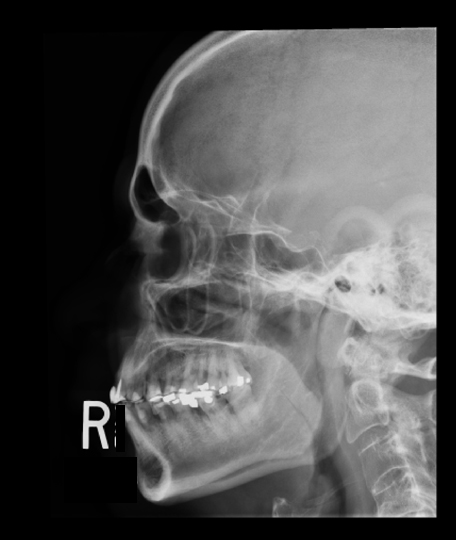

Identify the  Sinuses you see. Click on the image to see the labeled image.